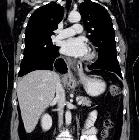

Postoperative

herniation of Nissen fundoplication. Retrocardiac structure completely surrounding the distal oesophagus, aparently in continuity with the gastric fundus. The rest of the gastric chamber was located infradiaphragmatic.